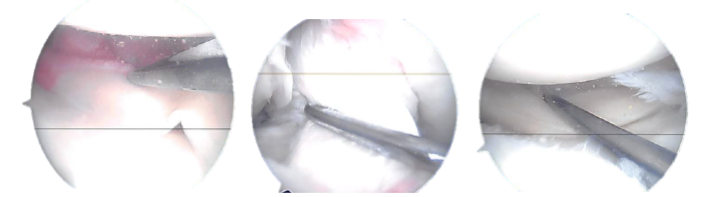

General anesthetic was administered. Over the right lower limb, a tourniquet was applied. Aseptically, the right lower limb was prepped and draped and Esmarch applied too. The knee joint was inspected and a lateral entry portal was established. A medial meniscus peripheral rupture was discovered.

A grade 1 to grade 2 median condylar osteochondral lesion of the femur was also found. The ACL had some fraying and degeneration. the healing of the medial meniscus. Sutures from Fast-Fix were used. The peripheral laceration from the posterior horn to the mid body was repaired with seven sutures.

Actual Arthroscopic images taken during the operation